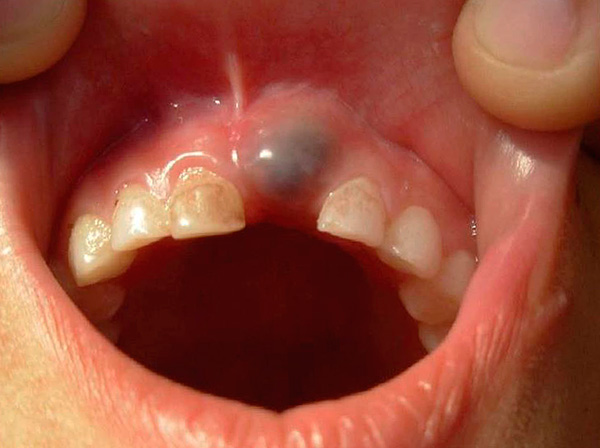

- Um cisto de dentição (uma cavidade preenchida com líquido) - quando um dente de dentição às vezes está descascando a camada subjacente da gengiva, forma-se um espaço preenchido com sangue, linfa ou, em casos graves, produtos de deterioração, ou seja, pus. A decisão sobre ir ou não ao médico nessa situação é tomada dependendo das condições gerais da criança. Basicamente, um cisto passa sem consequências, mas às vezes requer a intervenção de um especialista;